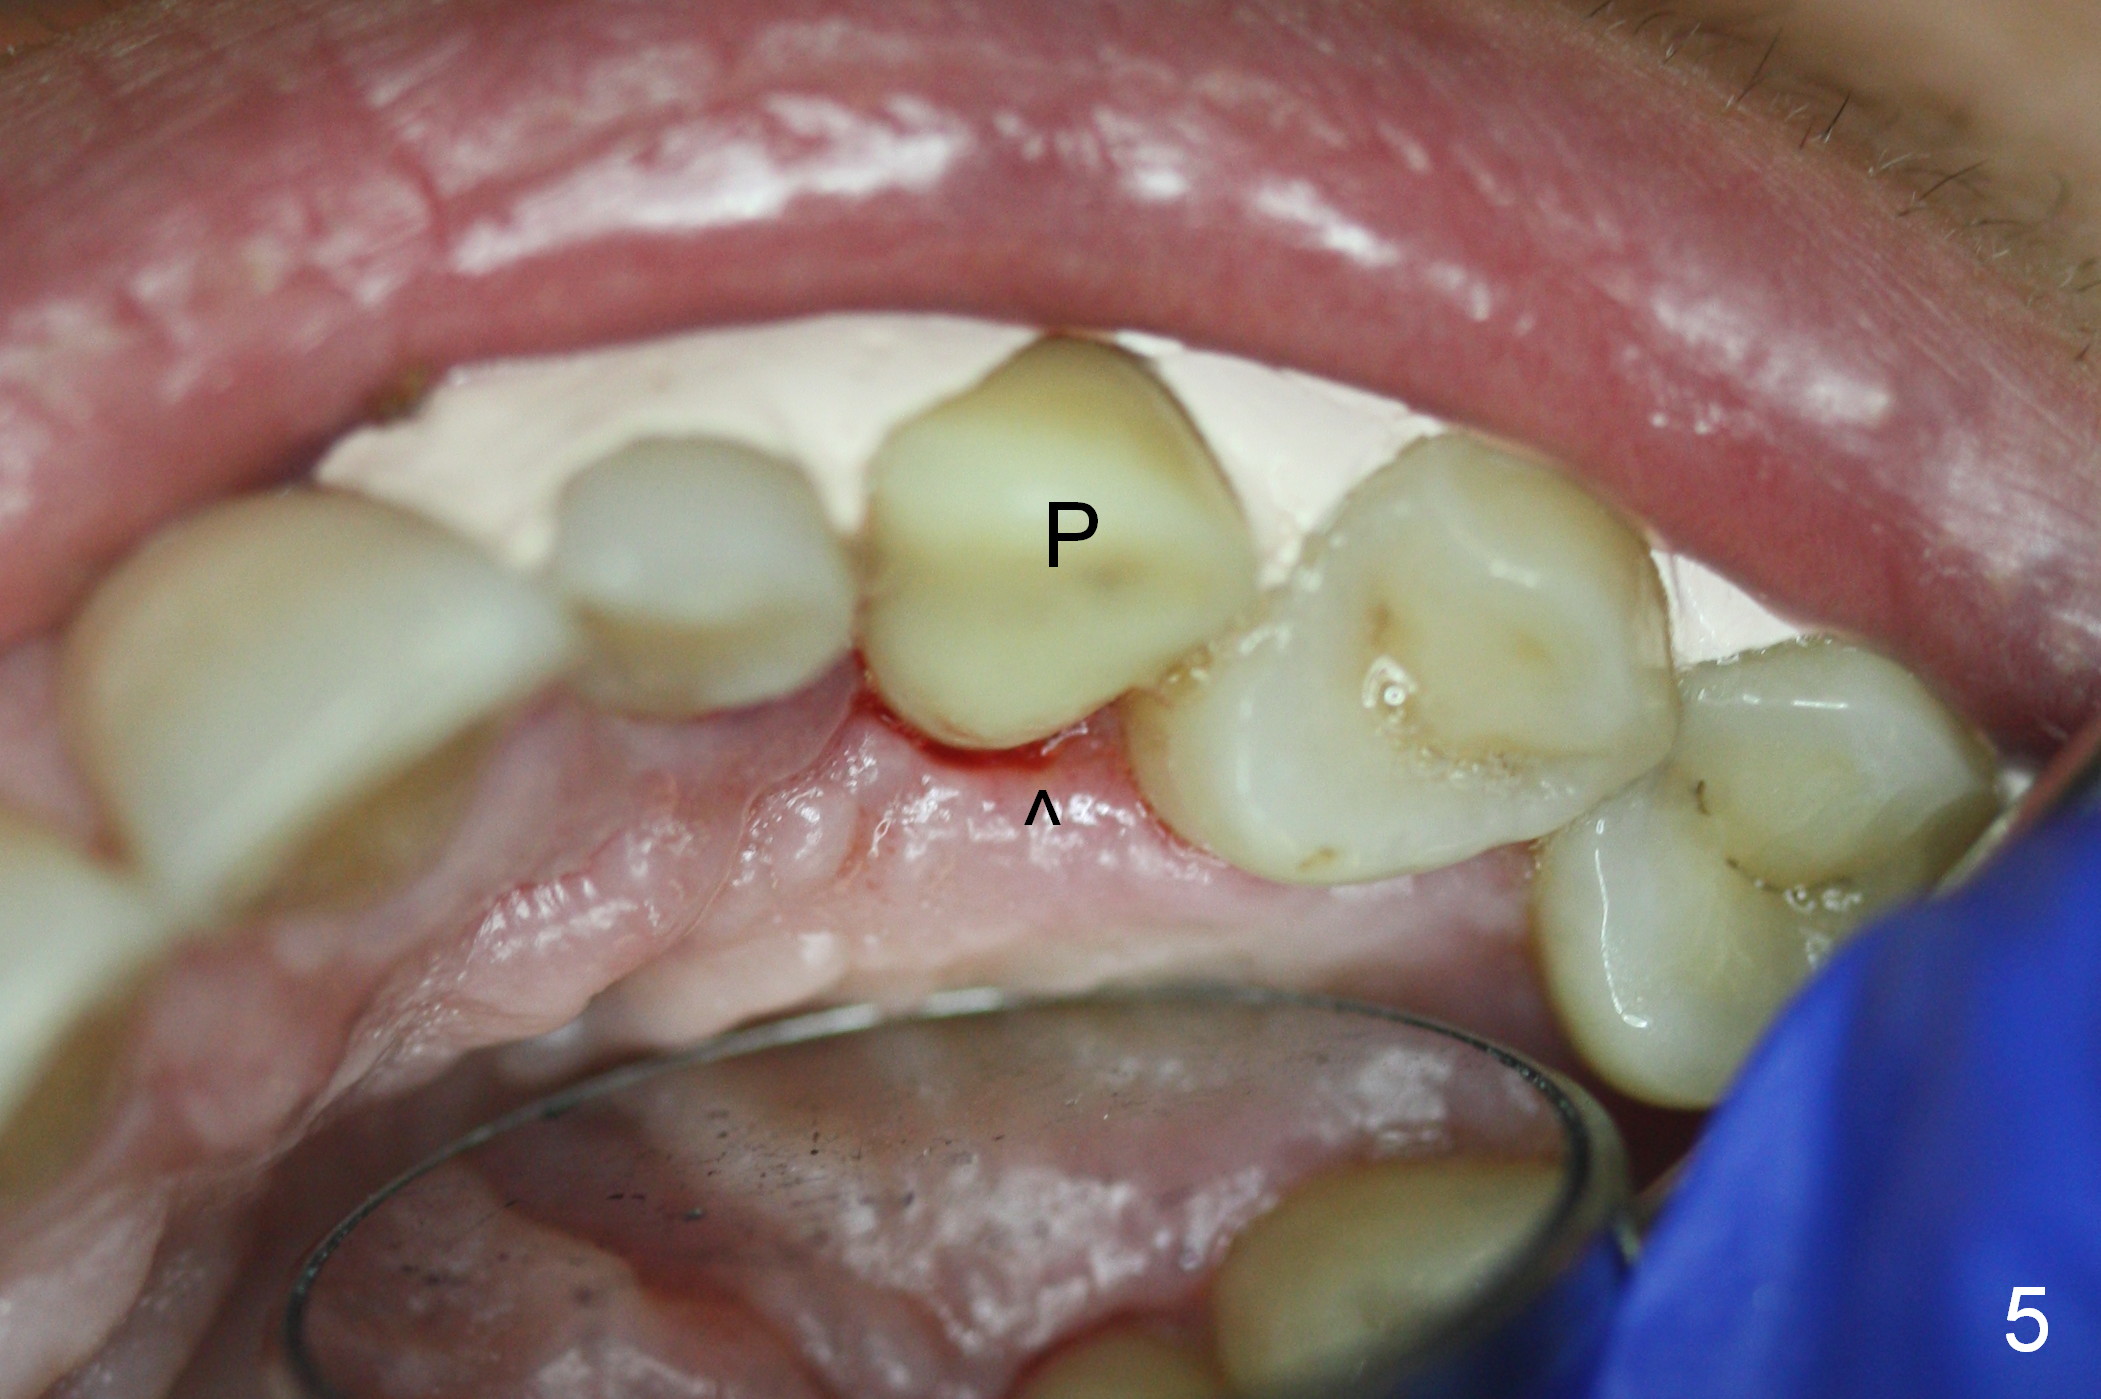

The ridge looks wide clinically 4 months post implant removal and socket preservation. In fact, the graft bone is soft and the ridge is narrow after incision. It appears that an angled 1 piece implant is an indication. A 1.2 mm pilot drill is used to start osteotomy. At approximately 17 mm, the patient feels pain. The nasal floor perforates? A 2 mm osteotome is utilized to enlarge the osteotomy. At 17 mm, the osteotome is stable (Fig.1), but the nasal floor appears out of view. Review of the preop PA shows that the distance between the gingival margin and the nasal floor (arrowheads) is ~22 mm (Fig.2). It should be safe and necessary to place a 3x20 mm 1-piece implant with 15° angulation. Insertion torque is between 40 and 45 Ncm.